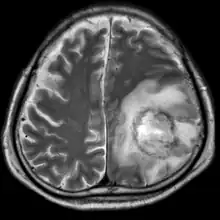

| T2-weighted MRI showing a necrotic brain absess as a result of GAE caused by an infection of Acanthamoeba, genotype T18 | |